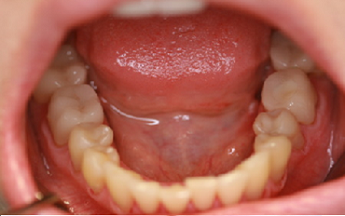

3) fotodokumentace - fotografie stavu chrupu a otisky na studijní modely

Fotodokumentace a model se provádí u pacientů s potřebou kompletní rekonstrukce chrupu.

Foto 9-13: Fotodokumentace situace v ústech - vlevo, vpravo, uprostřed, v horní a dolní čelisti.

Foto 14, 15: Vlevo zuby v úsměvu před ošetřením chrupu. Vpravo fotografie skusu zubů.